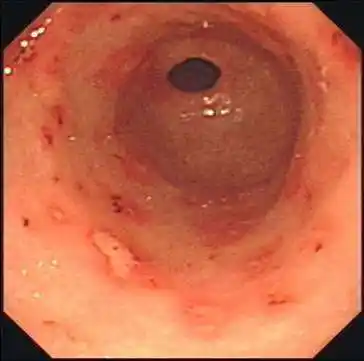

胃窦糜烂 (7)_有来医生

胃窦隆起糜烂